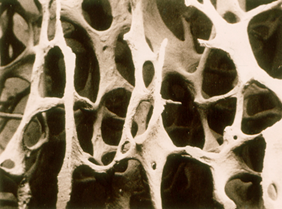

正常的骨结构

骨质疏松骨结构